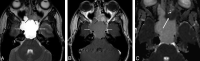

Background and purpose: The purpose of this work was to study differences in apparent diffusion coefficient (ADC) values between benign and malignant head and neck lesions at 3T field strength imaging.

Materials and methods: Our study population in this retrospective study was derived from the patient population who had undergone routine neck 3T MR imaging (for clinical indications) from December 2005 to December 2006. There were 33 patients identified: 17 with benign and 16 with malignant pathologies. In all of the subjects, conventional MR imaging sequences were performed apart from diffusion-weighted sequences. The mean ADC values in the benign and malignant groups were compared using an unpaired t test with unequal variance with a P < 0.05 considered statistically significant.

Results: There was a statistically significant difference (P = .004) between the mean ADC values (in 10(-3) mm(2)/s) in the benign and malignant lesions (1.505 +/- 0.487; 95% confidence interval, 1.305-1.706, and 1.071 +/- 0.293; 95% confidence interval, 0.864-1.277, respectively). There were 2 malignant lesions with ADC values higher than 1.3 x 10(-3) mm(2)/s and 5 benign lesions with ADC values less than 1.3 x 10(-3) mm(2)/s. The lack of overlap of ADC values within 95% confidence limits suggests that a 3T ADC value of 1.3 x 10(-3) mm(2)/s may be the threshold value for differentiation between benign and malignant head and neck lesions.

Conclusion: ADC values of benign and malignant neck pathologies are significantly different at 3T imaging, though larger studies are required to establish threshold ADC values that can applied in daily clinical practice.